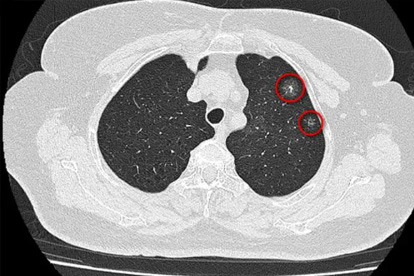

即使没有不适,25岁后也该每年做一次低剂量螺旋CT。有家族史的更要提前筛查,早期肺癌治疗几率可达90%。

那位20岁患者的病历显示,其实半年前就有晨起痰中带血的情况。当时如果及时检查,或许结局会完全不同。年轻不是健康的保险箱,改掉那些看似无伤大雅的坏习惯,才是对生命最好的投资。从今天开始,给娇嫩的肺部多些温柔呵护吧!